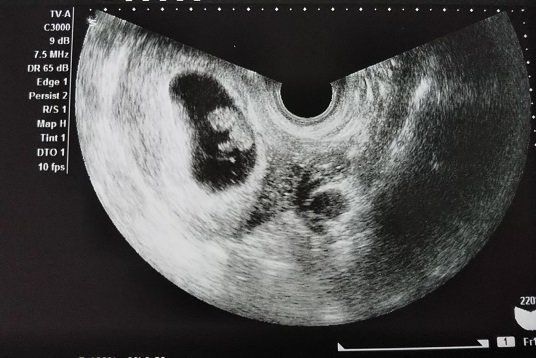

妊娠7週目のエコー写真 赤ちゃんの姿が!心音も聞かせてもらい、幸せを実感

妊娠7週目。初診で言われた2週間後の検診の日…。ドキドキしながらの受診でしたが、診察してもらうと、赤ちゃんの袋、胎嚢の中に赤ちゃんの姿が見えました!心音を聞かせてもらったときには、涙が出てきました。帰りには母子手帳をもらいに行って、うれしさいっぱいでした。